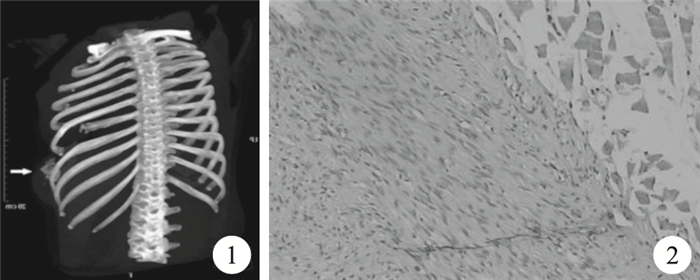

臨床資料??患者,女,現46歲。1998年11月發現右胸壁腫塊,伴疼痛。腫塊進行性增大,患者于2000年1月入院,胸部CT示“右側胸壁軟組織腫塊并侵犯第6、第7肋骨”。1月17日在全身麻醉下行右胸壁腫塊切除術,術中發現右胸壁腋中線至腋后線第4~7肋骨范圍巨大腫塊,約10 cm×8 cm×5 cm,與第6肋骨融合,破壞肋骨,并突入胸腔內生長,與肺無粘連。遂將右第6肋骨部分連同腫塊整塊切除。術后病理檢查示“高分化軟骨肉瘤”。患者術后未行放療,于1月31痊愈出院。2009年6月患者再次出現右胸壁包塊,并于2012年9月再次入住我科。肋骨三維CT示“右側第7肋骨部分骨質缺損,前外緣骨質明顯破壞并軟組織腫塊形成”(圖 1)。2012年9月18日在全身麻醉下行“右胸壁腫瘤切除+右側肋弓部分切除術”,術中見腫塊位于右胸壁腋中線至腋前線第第7~10肋骨范圍,大小約10 cm×8 cm×3 cm,向內侵犯壁層胸膜,但右肺、膈肌及腹腔內器官未見侵犯。腫塊切除后,胸壁缺損以患者自體胸大肌覆蓋修補,并加壓包扎,患者術后恢復順利。術后病理檢查結果示“侵襲性纖維瘤病”,免疫組織化學染色示:Actin、CD34陽性,S-100、Des、P53、Ki67陰性(圖 2)。后患者轉至腫瘤科行放療,放射劑量為4 000 cGy,持續時間4周,于2012年11月9日治愈出院。半年后隨訪,患者目前尚未有再次復發的征象。

圖1

肋骨三維CT??圖 2??病理檢查結果